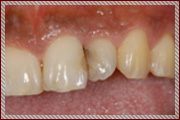

スポーツ中に前歯を折ってしまったケース

スポーツ中に相手の肘が前歯にぶつかってしまい、折れて粉々に砕けてしまった。

外傷で歯は折れてバラバラに砕けてしまっているが幸い破片はぴったりと合う状態

歯科用接着剤を使用して歯の形態を回復した

整復固定直後

術後

| 治療期間 | 2ヶ月 |

|---|---|

| 費用 | 5万円(スポーツ振興保険適用時は負担無し) |

| メリット | 被せ物やインプラントではなく自分の歯で治すことができる |

| デメリット | 受傷状態や歯の保存状態によっては再着できないことがある |